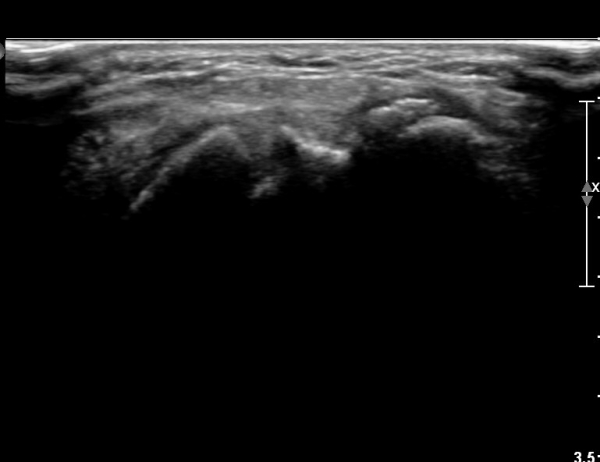

¼Õ¸ñ Ⱦ´Ü¸é°Ë»ç»ó ÁÖ»ó°ñ¿ù»ó°ñ Àδë´Â Á¤»óÀûÀ¸·Î °üÂûµÇ³ª ¿ù»ó°ñ»ï°¢°ñ ÀÎ´ë ºÎÂøºÎ

¿ù»ó°ñ ÇÇÁú°ñÀÇ ºÒ±ÔĢȭ¿Í »ï°¢°ñ Ç¥ÃþÀÇ °ñÆíÀÌ °üÂûµÈ´Ù(»çÁø 3).